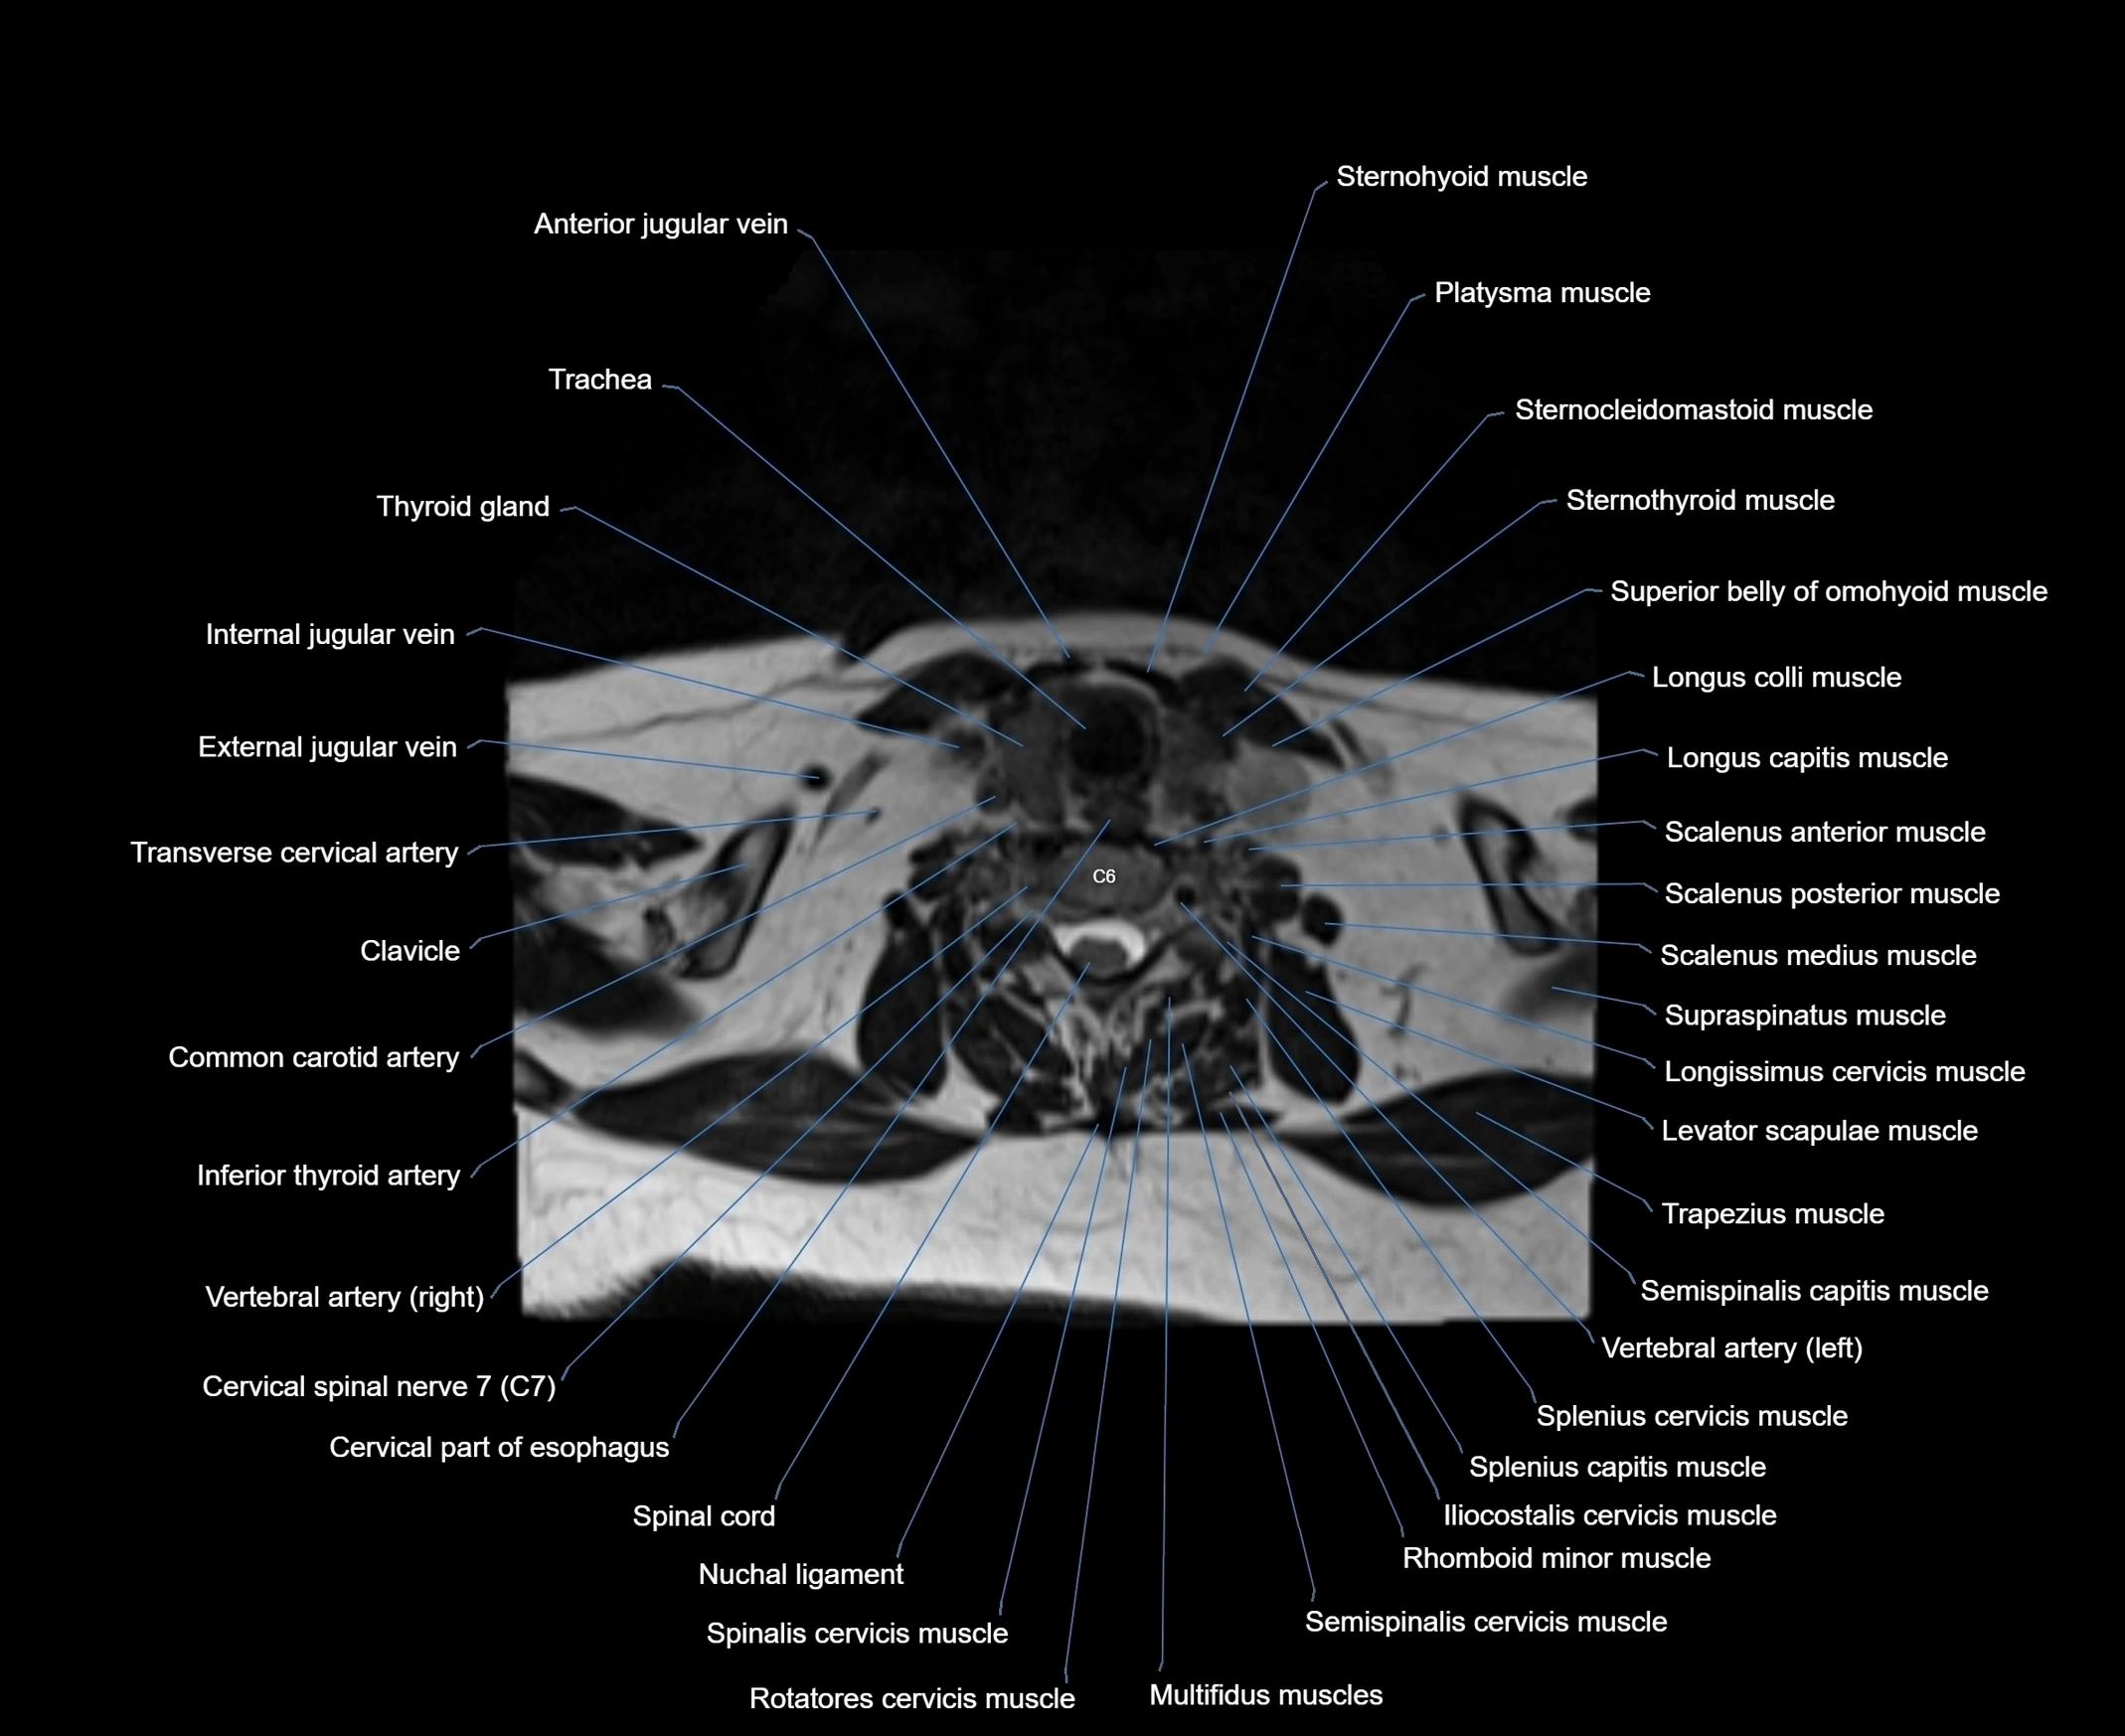

- Anterior jugular vein

- Cervical part of esophagus

- Cervical spinal nerve 7 (C7)

- Common carotid artery

- External jugular vein

- Iliocostalis cervicis muscle

- Inferior belly of omohyoid muscle

- Inferior thyroid artery

- Levator scapulae muscle

- Longissimus cervicis muscle

- Longus capitis muscle

- Longus colli muscle

- Multifidus muscles

- Nuchal ligament

- Platysma muscle

- Rhomboid minor muscle

- Rotatores cervicis muscle

- Scalenus anterior muscle (Anterior scalene muscle)

- Scalenus medius muscle (middle scalene muscle)

- Scalenus posterior muscle (Posterior scalene muscle)

- Semispinalis cervicis muscle

- Spinal cord

- Spinalis cervicis muscle

- Splenius capitis muscle

- Splenius cervicis muscle

- Sternocleidomastoid muscle

- Sternohyoid muscle

- Sternothyroid muscle

- Superior belly of omohyoid muscle

- Supraspinatus muscle

- Thyroid gland

- Trachea

- Transverse cervical artery

- Trapezius muscle